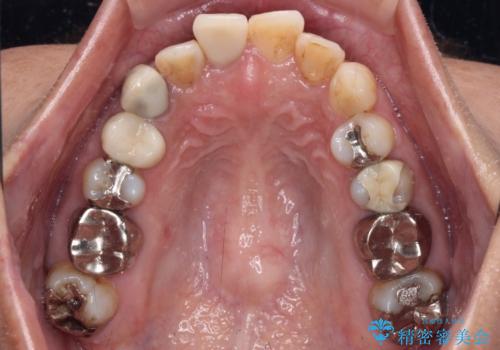

- 上下前歯のデコボコを気にして来院された患者様です。

歯列としては、ワイヤー装置でもインビザラインでも、どちらでも対応可能でしたが、処置されている歯が多く、ワイヤー装置を装着するためには処置歯のやり直しが必要な状態でした。

インビザラインでもアタッチメントを装着できないという同様のデメリットがありますが、比較的矯正治療を行いやすい歯列であったので、インビザラインによる矯正治療を行うこととしました。